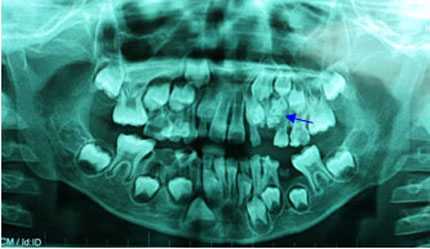

Ảnh chụp X quang hàm răng của bé trai 7 tuổi.

Bé được tiến hành chụp phim X-quang để khảo sát. Trên phim toàn cảnh, bác sĩ phát hiện có một khối cản quang không đồng nhất, giới hạn tương đối rõ, ở vùng xương hàm trên bên trái, và nằm cạnh khối u là chiếc răng nanh sữa, đó chính là chiếc răng mà bác sỹ đang quan tâm tìm hiểu.

Khối cản quang đó được chẩn đoán là u răng, một loại u răng sinh lành tính thường gặp ở vùng xương hàm.